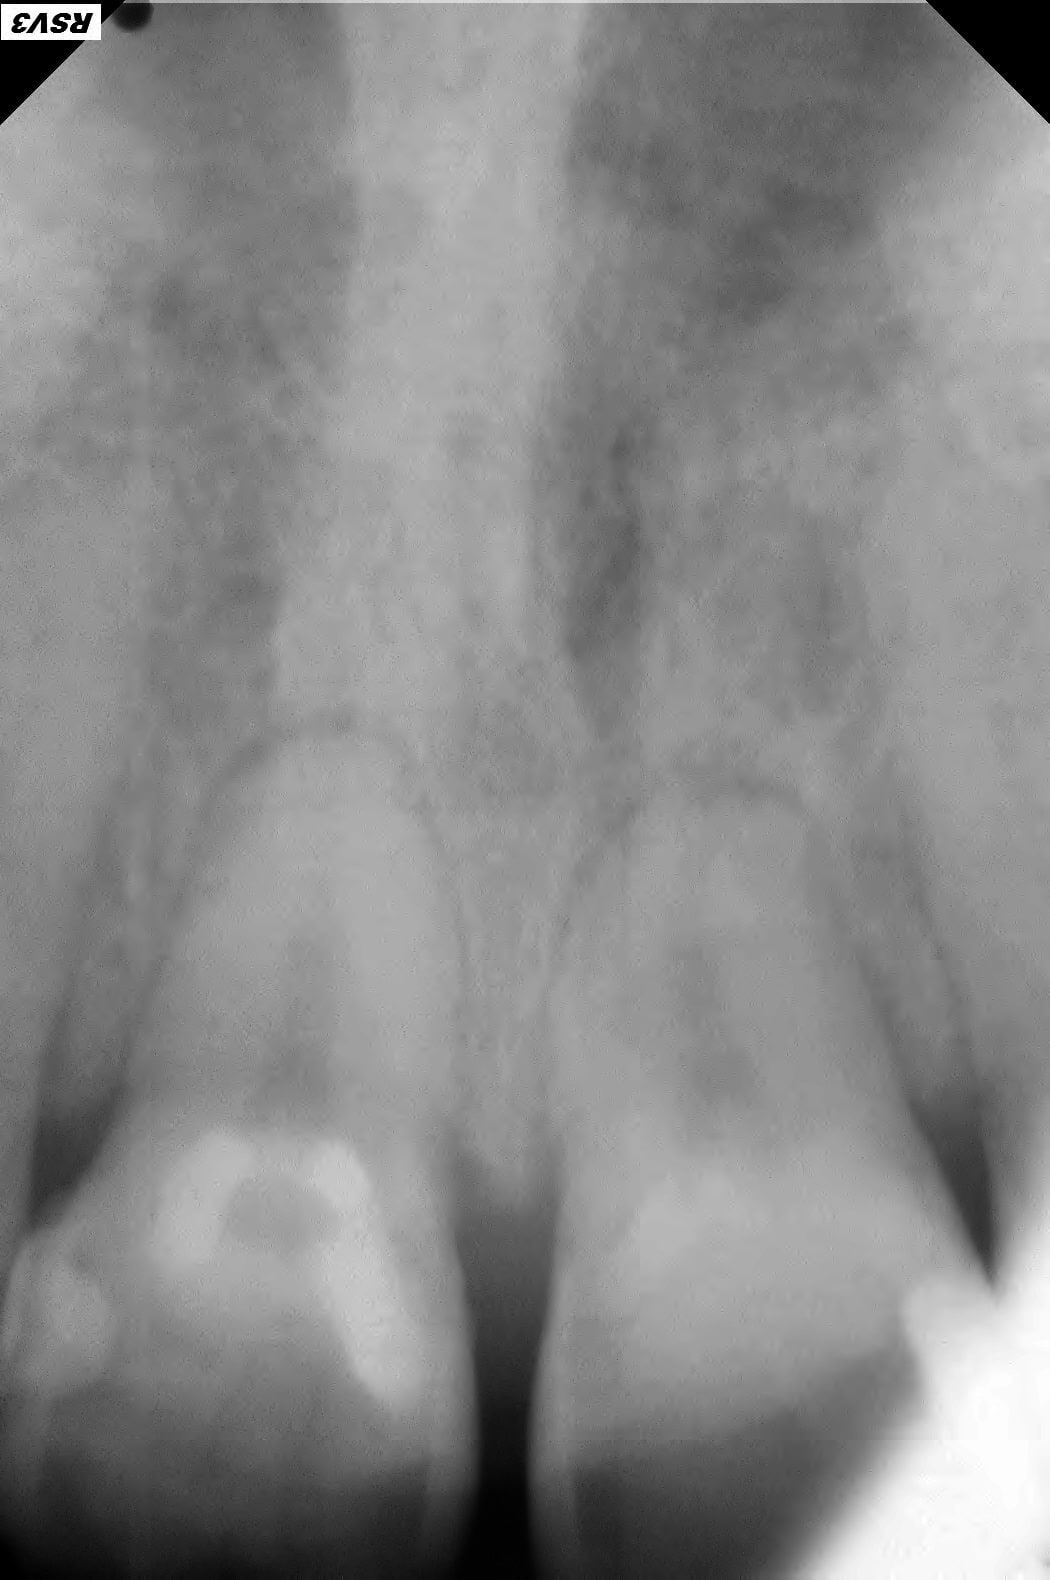

Patient 40 ans , fumeur, ex fan du coca, stressé, bruxomane forcené qui présente des érosions et abrasions chimiques généralisées.

Suite l'abrasion des dents postérieures il a une surcharge sur 11 et 21 qui sont devenues mobiles avec en plus des racines résorbées.

Elles sont bien angulées tes RX sur 11-21?

1/ Toutes les dts st abrasées, pas ou peu de déchaussement gingival et mobilité des incisives sup, pas de résorption radiculaire plutôt une arthrite ligamentaire. Pronostic de perte des incisives engagé à moyen terme.